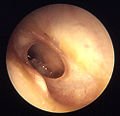

Otitis media with effusion

Otitis media with effusion (OME), also called serous or secretory otitis media (SOM), is simply a collection of fluid that occurs within the middle ear space as a result of the negative pressure produced by altered Eustachian tube function. This can occur purely from a viral URI, with no pain or bacterial infection, or it can precede and/or follow acute bacterial otitis media. Fluid in the middle ear sometimes causes conductive hearing impairment, but only when it interferes with the normal vibration of the eardrum by sound waves. Over weeks and months, middle ear fluid can become very thick and glue-like (thus the name glue ear), which increases the likelihood of its causing conductive hearing impairment. Early-onset OME is associated with feeding while lying down and early entry into group child care, while parental smoking, a short period of breastfeeding and greater amounts of time spent in group child care increased the duration of OME in the first two years of life.[1]